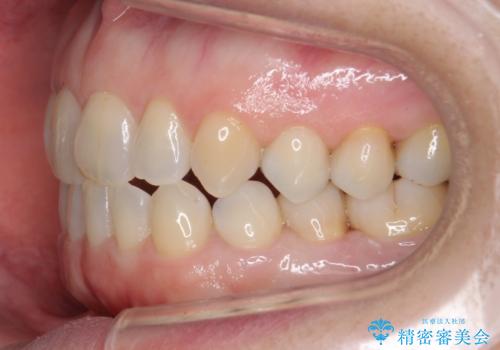

- 右上の2番目の前歯がとがった形をしていたため、セラミックで形を整えています。

短くてとがった歯の形が反対側と同じ形となり、左右対称となり、ずいぶん自然な印象になりました。

下の前歯とのかみ合わせが切端咬合だったため、前歯の部分矯正も併せて行っています。(費用別途)